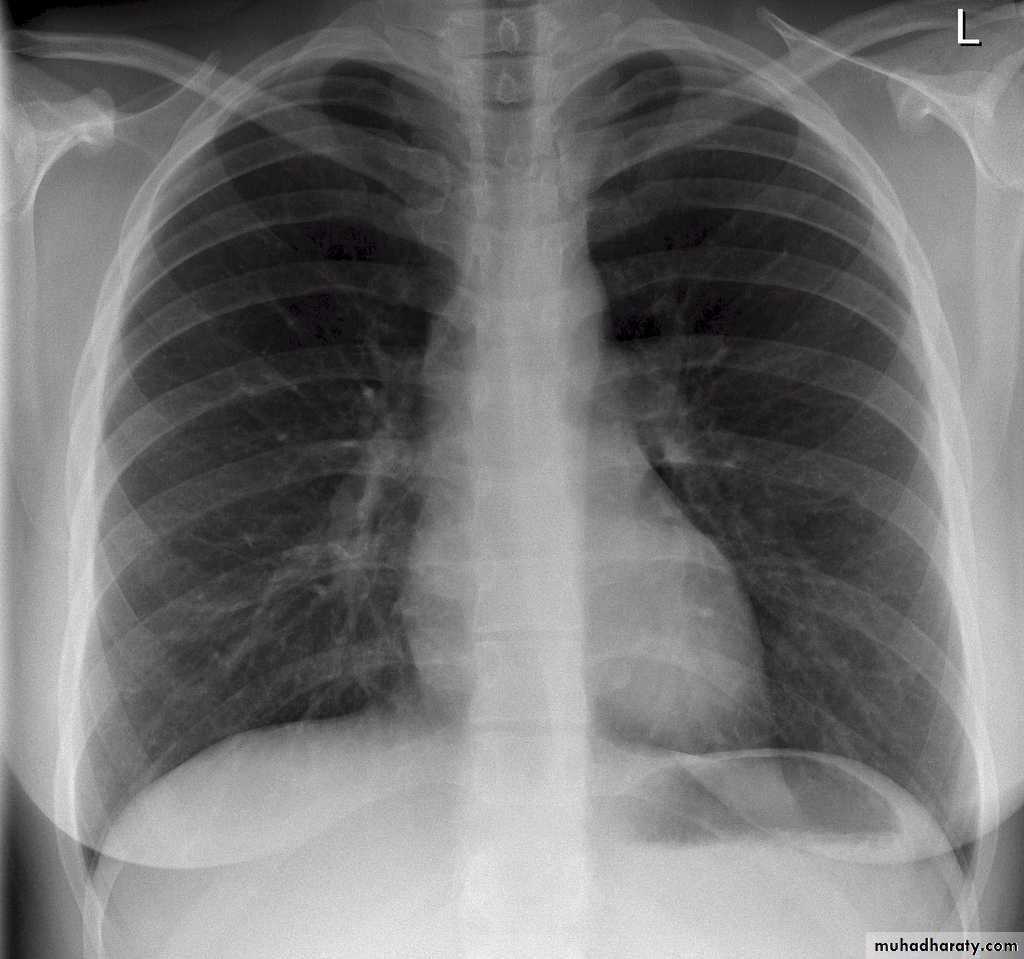

5)Full inspiration

The diaphragm should be below theanterior end of 6th rib & posterior end of 10th rib .

In expiratory film there is cardiac shadow enlargement , & vascular crowdening

Poor visualization of bases of the lungs1